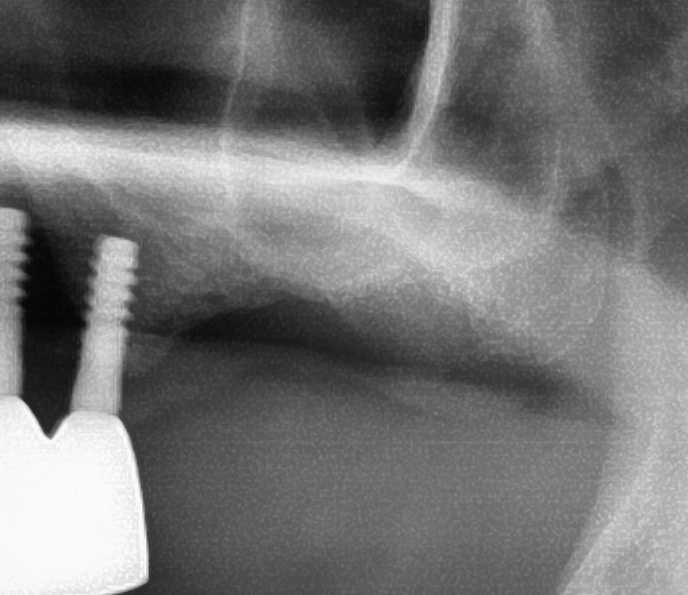

開けた穴に、専用道具を使ってネジを締めるように長さ2センチ程のインプラントを骨に埋め込んでいきます。

しっかりとインプラント埋め込まれた後は、動揺がないか、噛んだ時に当たらないかなどを確認して、最後にパノラマ写真を撮影して今回のオペは終了となりました。